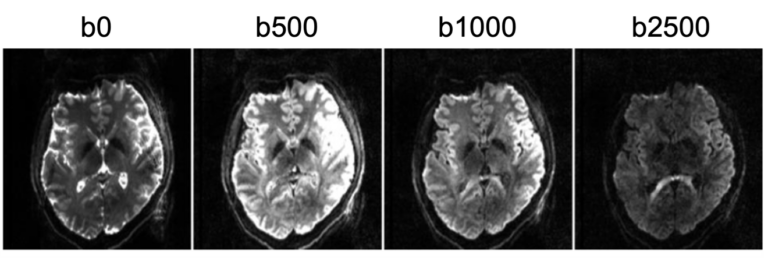

We are happy to announce that our lab just has received funding for a new DFG project as part of our new DFG research unit (RU) “Fast Mapping of Quantitative MR biosignatures at Ultra-high Magnetic Field”. In our joint subproject together with Frederik Laun [link], we will develop DWI and QSM at 7T with unprecedented […]We are happy to announce that our lab just has received funding for a new DFG project as part of our new DFG research unit (RU) “Fast Mapping of Quantitative MR biosignatures at Ultra-high Magnetic Field”. In our joint subproject together with Frederik Laun [link], we will develop DWI and QSM at 7T with unprecedented […]